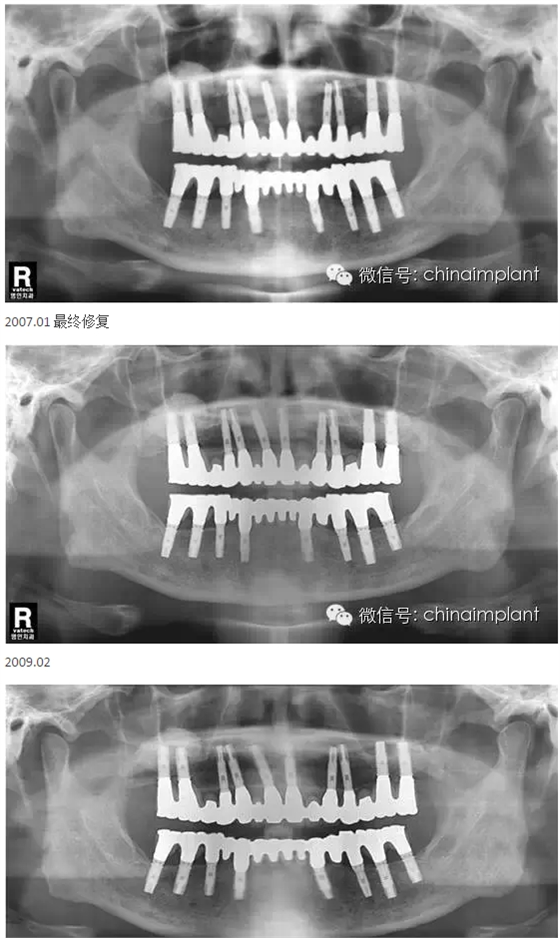

之前針對全口無牙進(jìn)行種植修復(fù)的案例中,因?yàn)轭M骨的原因,后期使用橋冠修復(fù)時(shí),一般是3部分(兩側(cè),磨牙,前牙),最近的案例中修復(fù)是一般都是做一體式的橋冠,現(xiàn)在從臨床的修復(fù)案例來看,沒有什么問題。

之前的時(shí)候,使用圓錐形基臺,但是附著的力量容易分散。(最近由于費(fèi)用的問題多使用UCLA形態(tài)的基臺)

本案例已經(jīng)將近10年了(2005年12月),但是修復(fù)效果個(gè)人認(rèn)為很不錯(cuò),所以拿出來和大家分享。

從修復(fù)全景片上看到牙齒排列非常好